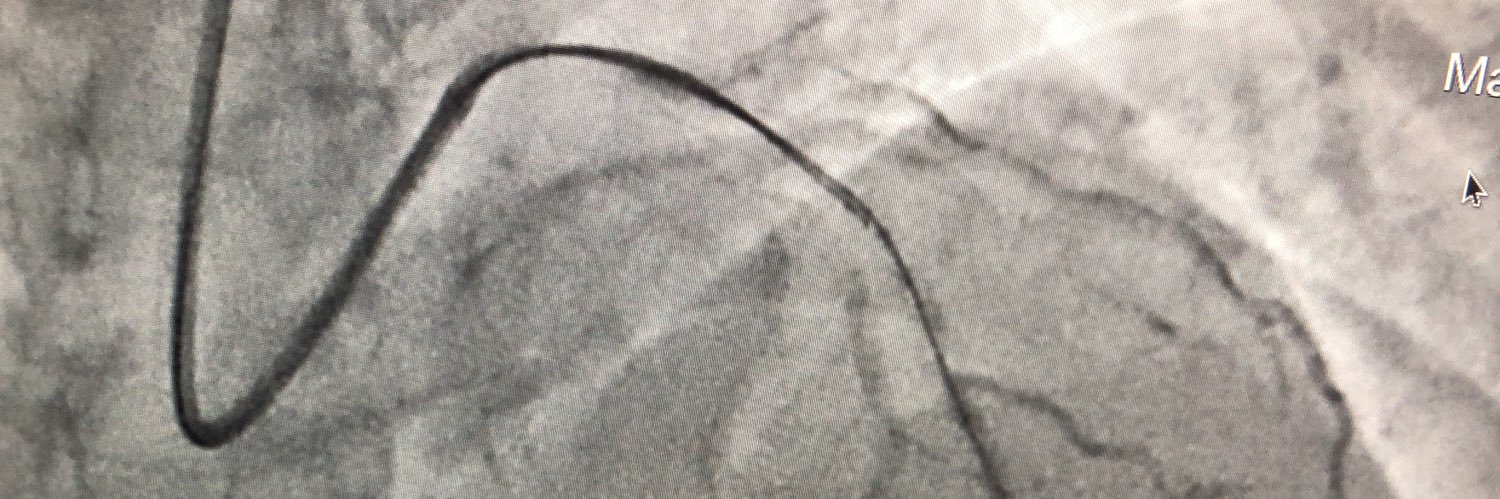

Elad Maor

Elad Maor@maor_elad·

A true nightmare in the cath lab: 50M with inferior STEMI, normal coronaries, then collapsed. Aortogram clip speaks for itself. The saying goes, 'If you haven’t faced it in the cath lab, you haven’t seen enough cases.' @yonigros @PCRonline @mandeep_mayo

mandeep singh

mandeep singh@mandeep_mayo·

@maor_elad @yonigros @PCRonline It is indeed horrifying. Iatrogenic Type A dissection, now involves aortic valve, coronaries&arch. Bad prognosis. Not sure the sequence of events! Coronaries must have been injected through true lumen. My bucket list of complications that I haven’t done/seen is getting smaller